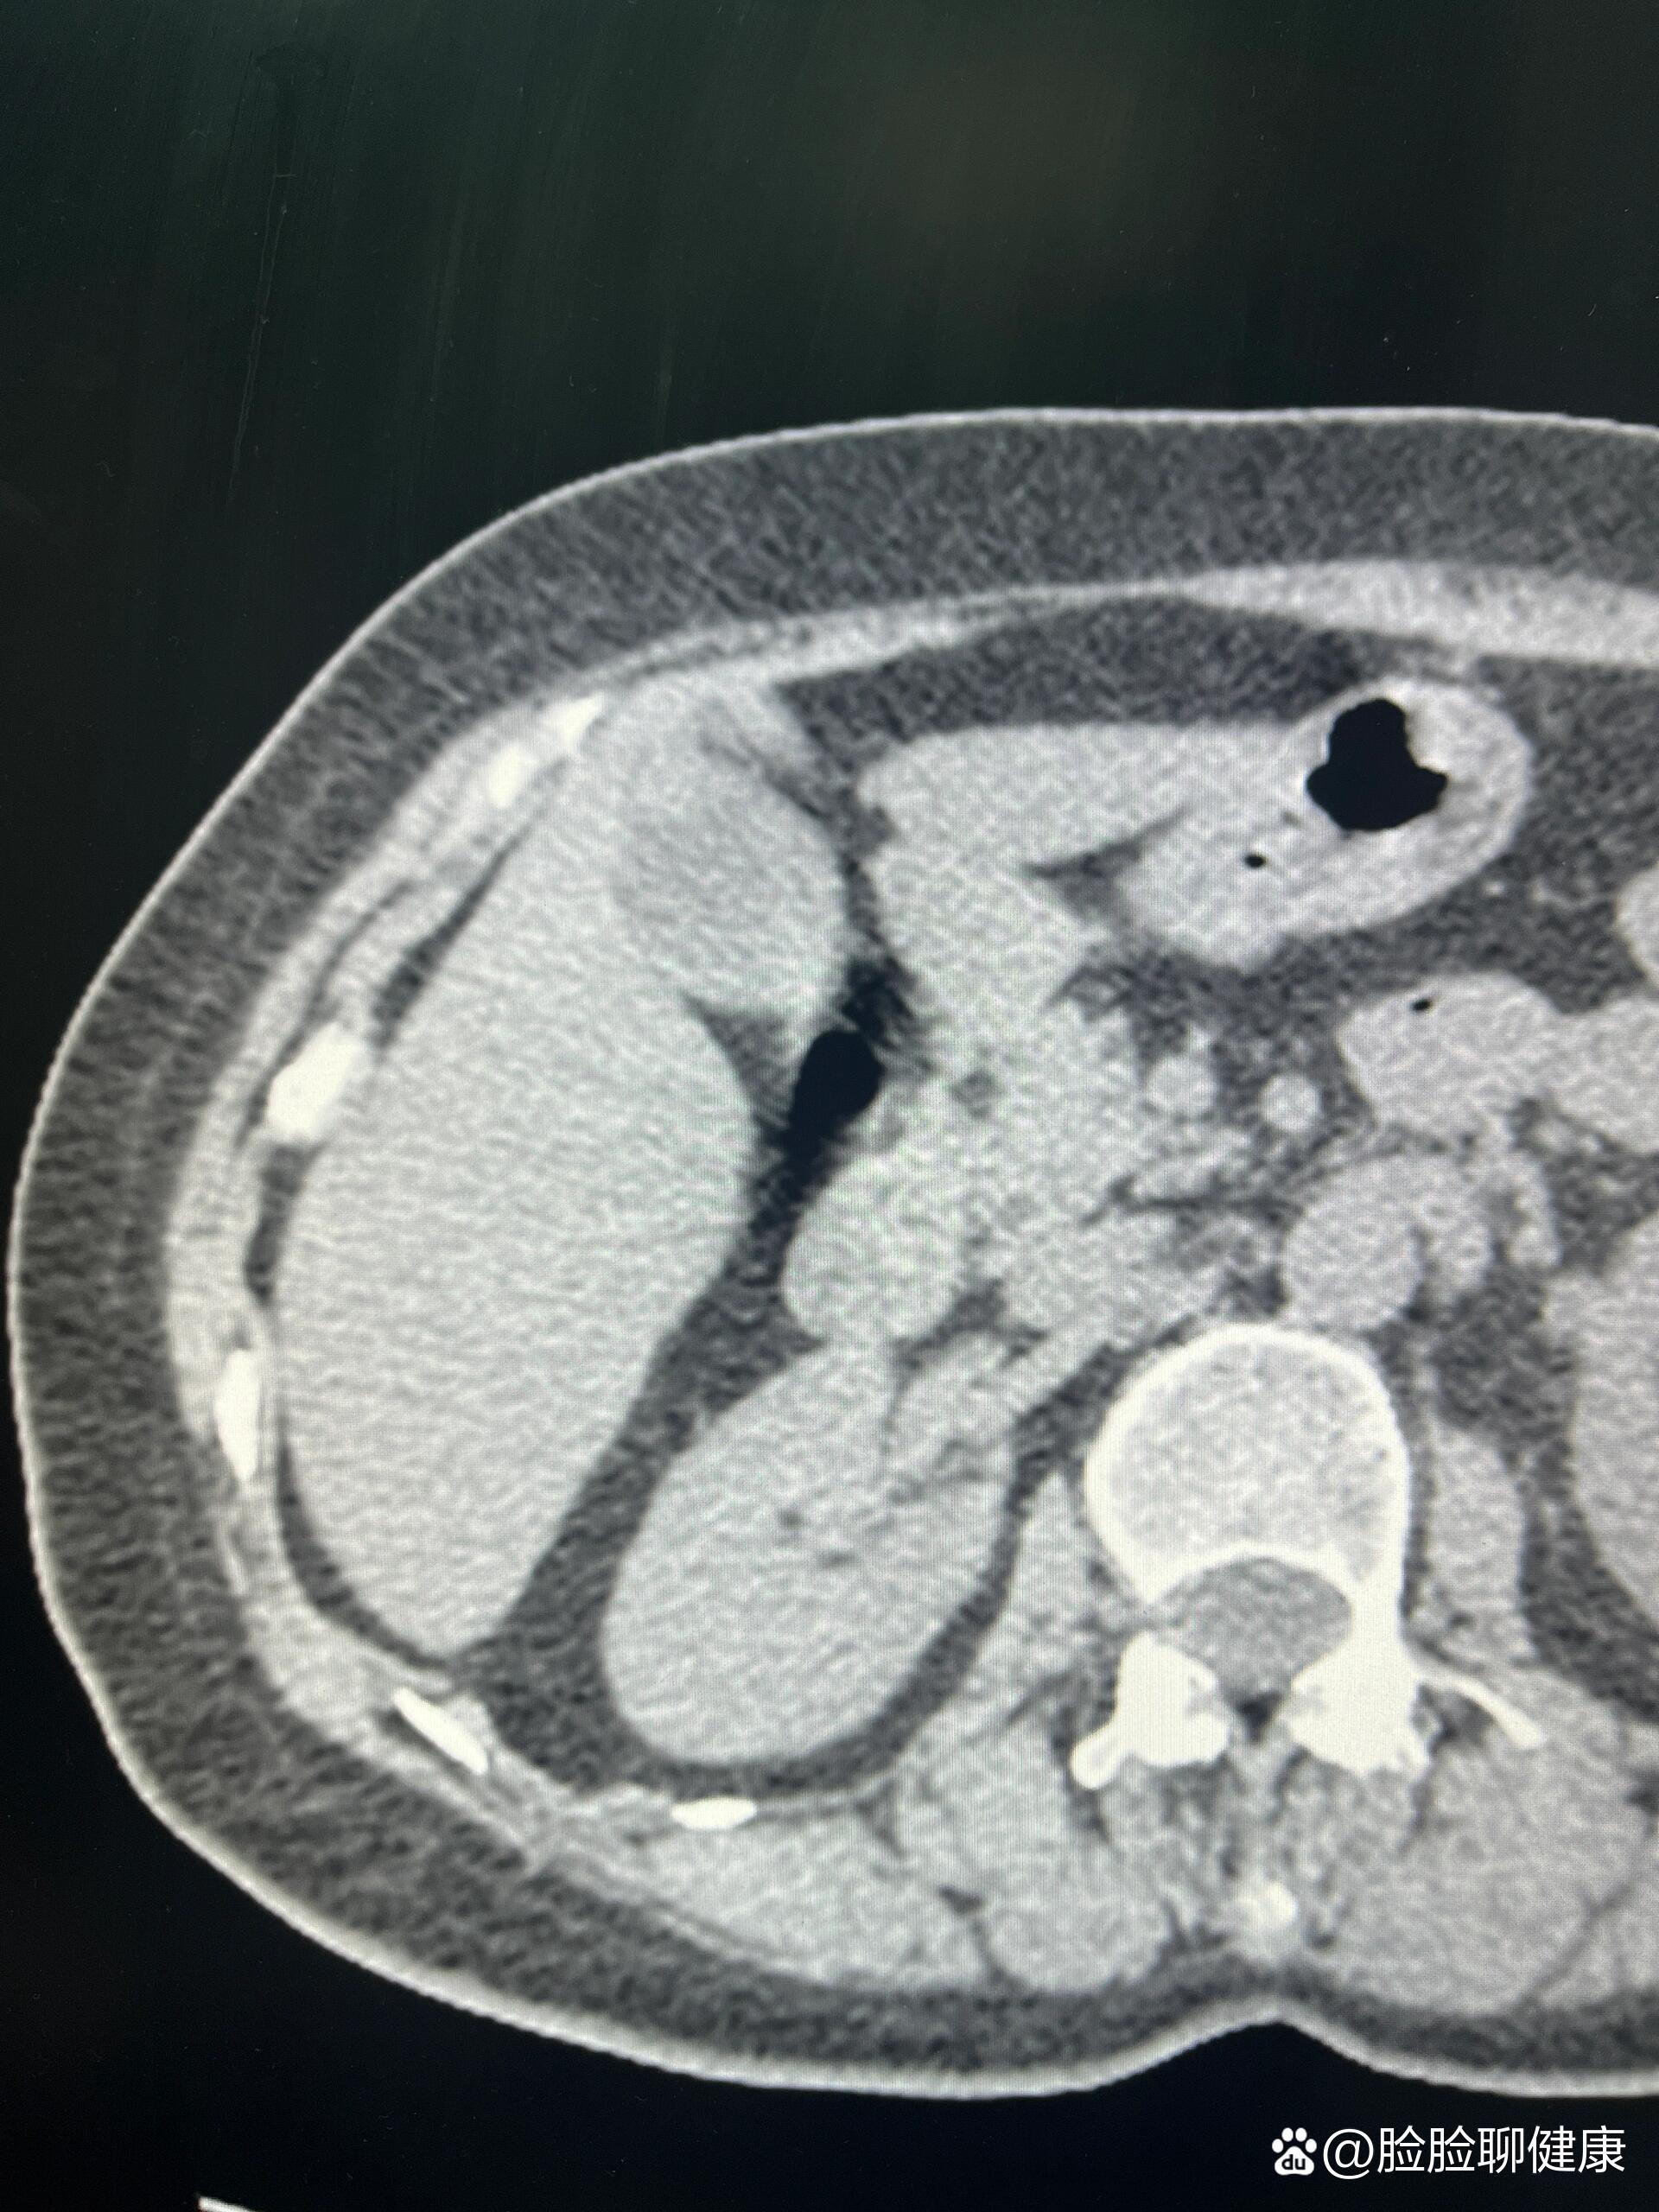

【病例】胆囊腺肌症1例ct影像表现

病例胆囊腺肌症1例ct影像诊断

ct和mri也用于表现不典型的胆囊腺肌症的诊断,主要协助排除胆囊癌.